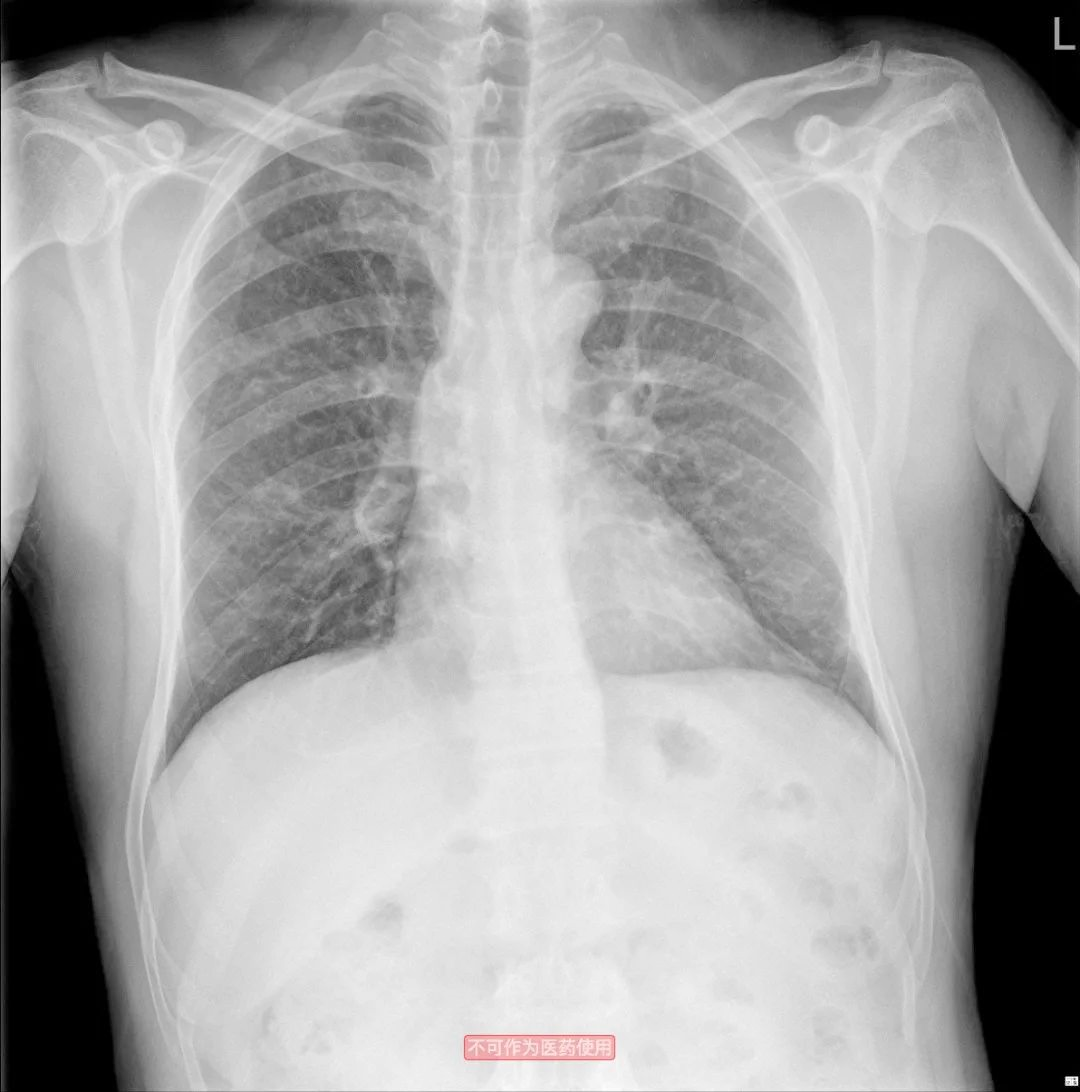

9月26号胸部CT明显好转后出院。

12月21日复查的胸片,基本正常。